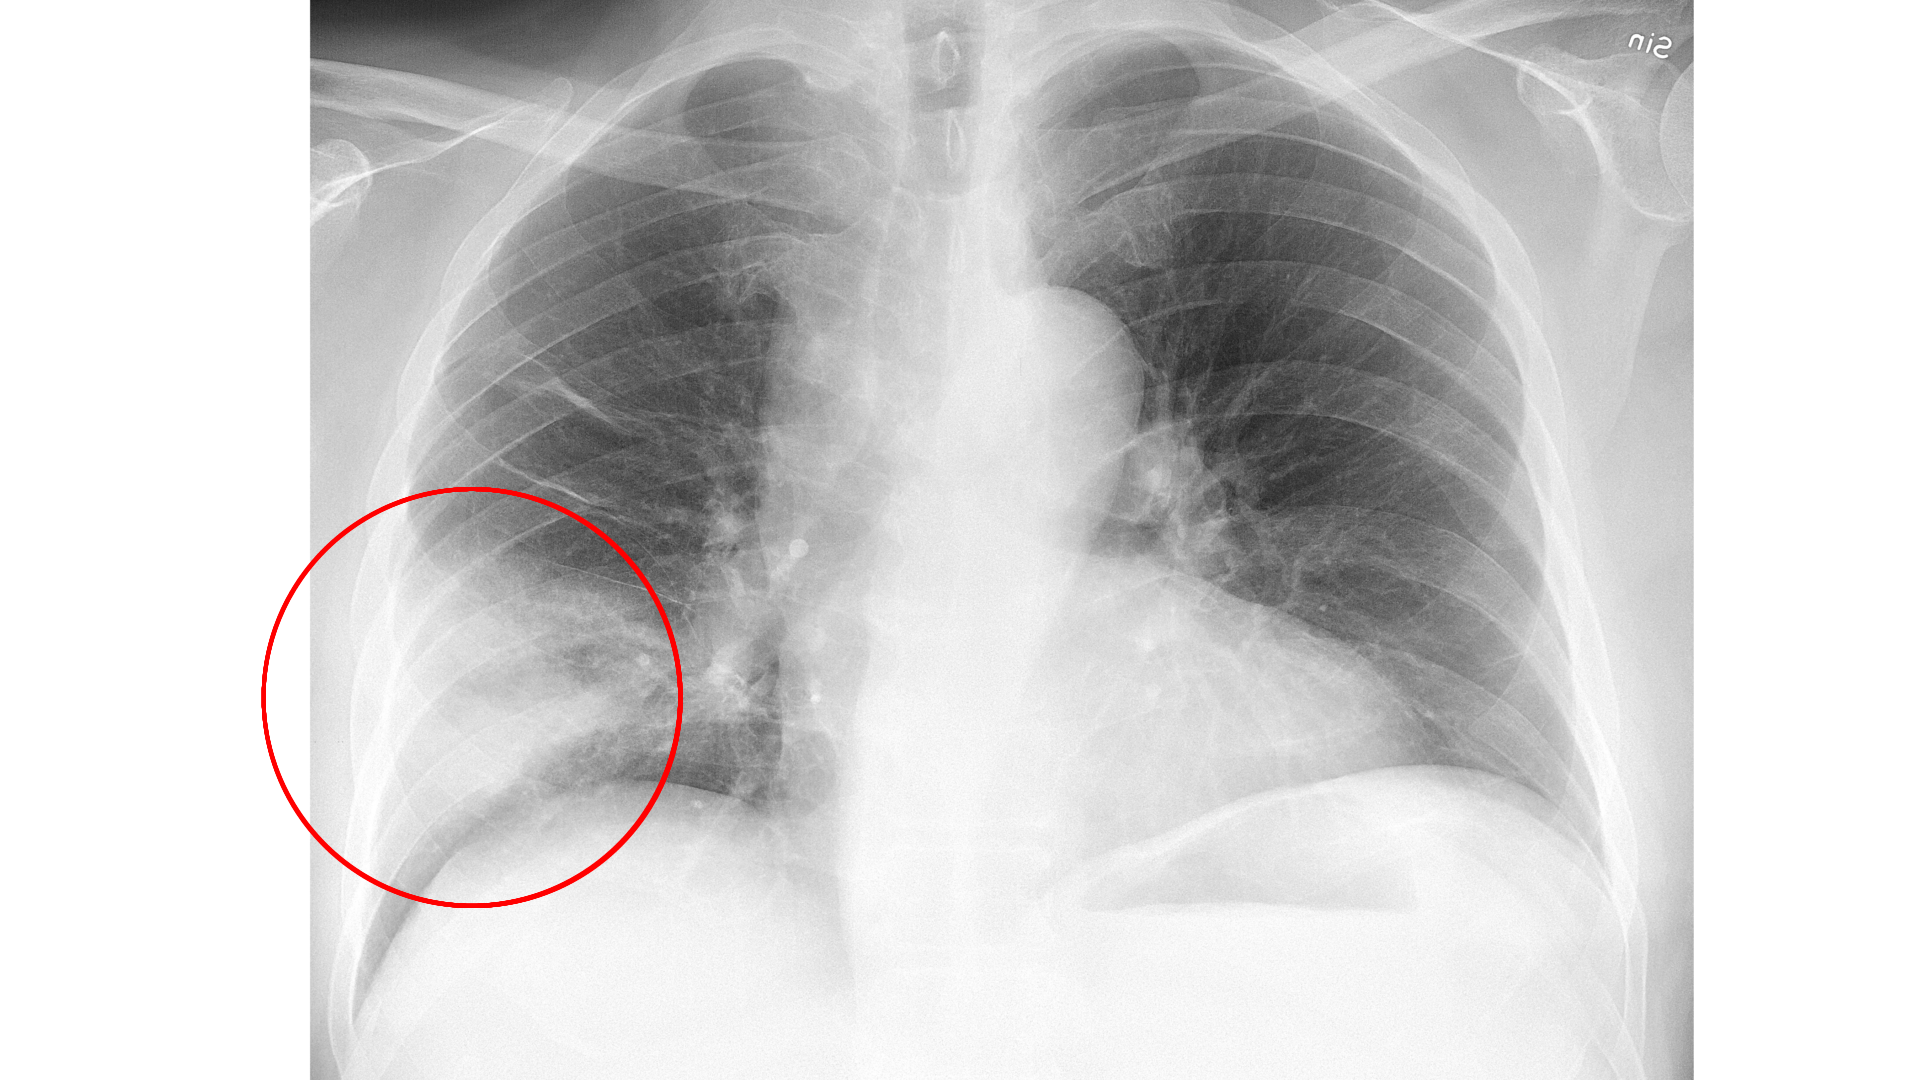

폐렴균만 폐렴을 일으키나?

- 폐렴은 꼭 폐렴구균 때문만 생기는 것은 아닙니다. 마이코플라즈마, 클라미디아, 포도상구균, 심지어 바이러스에 의해서도 올 수 있는데, 이런 경우는 흔하지 않아 따로 백신으로 예방하지는 않습니다.

- 고열과 심한 기침, 흉통처럼 단순 감기라고 보기에 심한 증상이 나타난다면 지체하지 말고 병원을 찾아 정확한 진단을 받고 항생제나 항바이러스제 치료를 받는 것이 안전합니다.